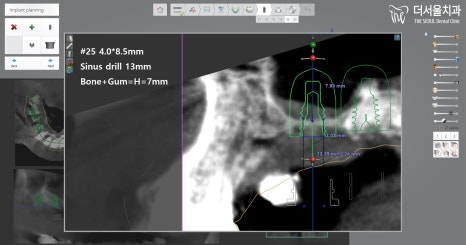

컴퓨터 분석을 이용하여

임플란트 식립을 어떻게 하면 좋을지

계획을 꼼꼼히 수립해나갔습니다.

곳곳마다 현재 가지고 있는 뼈의 양,

어떤 재료로 심어줘야 되는지,

골이식을 얼마만큼 해야 되는지,

미끌림은 없을지,

추가로 진행해야될 다른 진료는 없는지

꼼꼼히 확인 후 계획을 수립하였습니다.